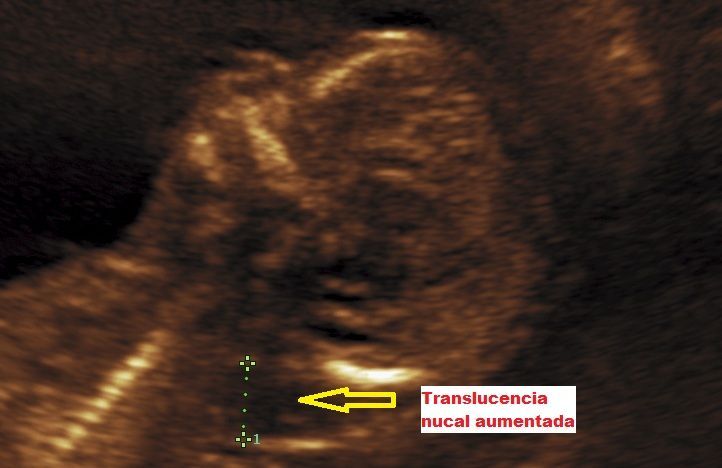

Realizamos las ecografías de viabilidad del embarazo, genética, morfológica, de bienestar fetal, ecocardiografías fetales, así como procedimientos invasivos como biopsia de vellosidades coriales y amniocentesis.